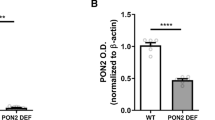

Reduced expression and in vivo activity of TH in mpFC of ENU2 mice. (a) Schematic representation of mpFC. (b) Western blot of TH protein obtained from mpFC of ENU2 and WT mice and (c) quantification of protein using chemiluminescence (mean ± S.E.M.) indicated reduced enzyme availability in mutant mice. Detection of β-actin was used as loading control. (d) Enzymatic activity of TH was determined measuring accumulation of transient intermediate L-DOPA in vivo during continuous infusion of 20 µM NSD-1015. Dialysates were collected at 20-min intervals. Results are expressed as percent changes (means ± S.E.M.) from basal values. Statistical analyses were performed on raw data. Comparison of time course of changes in extracellular levels of L-DOPA in pFC of ENU2 and WT mice reveals reduction of L-DOPA accumulation in ENU2 mice, significant from 160 min onwards. * P < 0.05 versus basal values. § P < 0.05 in comparison with WT

Expression and in vivo activity of TH in mpFC of ENU2 and WT mice

Western blot analysis of TH protein (Fig. 1b, c) showed significant difference between the two genotypes (F1,10 = 11.25, p < .01), revealing a 40 % reduction of TH protein levels in mpFC of ENU2 (1.84 ± .21) in comparison with WT (1.10 ± .06) mice.

Second, based on demonstrations that tyrosine is not the limiting factor on DA biosynthesis (Joseph and Dyer 2003; Pascucci et al 2009), we investigated cortical availability and activity of TH. Analysis of Western blot data confirmed reduced TH protein levels in mpFC of PKU mice (Joseph and Dyer 2003). Although the decreased protein amount of TH could be an adaptive downregulation in response to reduced dopaminergic synthesis, a faster degradation of the TH protein could not be excluded. Moreover, in vivo assay of TH cortical activity (measured as accumulation rate of L-DOPA after blockade of the decarboxylating enzyme) showed significant reduction in the rate of DA synthesis in ENU2 vs WT mice. The reduction of L-DOPA accumulation (66 %) was greater than the 40 % reduction seen in TH protein concentration suggesting other mechanisms causing TH inhibition. This most likely involves a direct inhibitory effect of phenylalanine on mpFC TH activity.